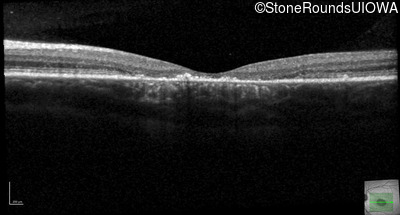

Optical Coherence Tomography - Right - 20/160 -1 sc

Exemplar / OCT Stack